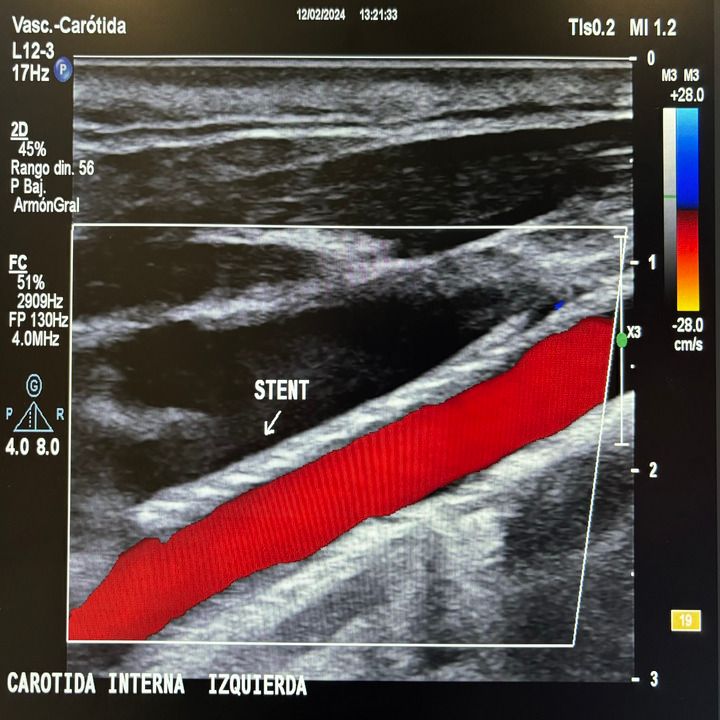

• Cirugía endovascular

• Diagnóstico vascular no invasivo